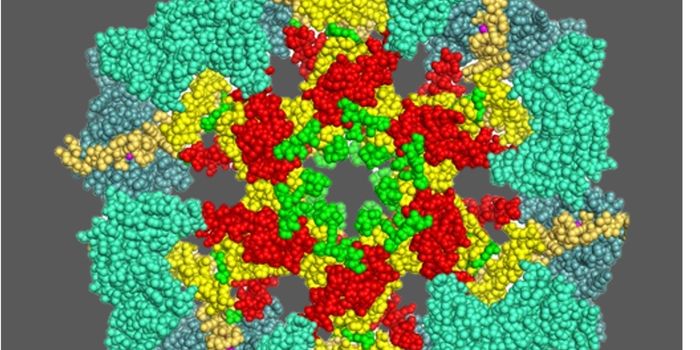

SEP 09, 2024Drug Discovery & DevelopmentThere’s No Turning Back Not long ago, solving the crystal structure of a protein required an entire PhD. Gro ...